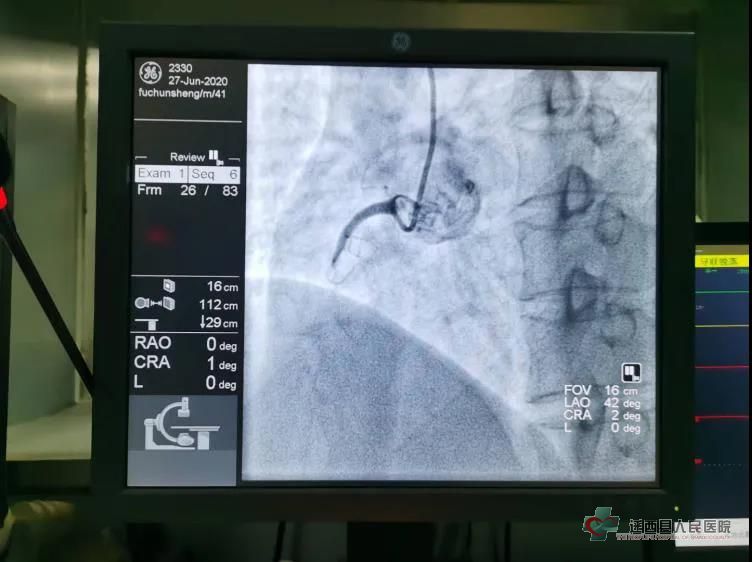

术者付彬彬,助手刘瑞超,介入护士员雅静、赵海伟有条不紊的在手术间进行操作。 造影提示:右冠中段完全闭塞,可见大量血栓影。

张主任和蔡主任在工作室有序的指导术者在血栓抽吸的基础上给予尿激酶原冠脉内靶向溶栓治疗,并积极有效的纠正了术中出现的严重缓慢性再灌注性心律失常。

再次造影提示:右冠中段可见钙化斑,狭窄程度小于50%,血流恢复至TIMI3级。